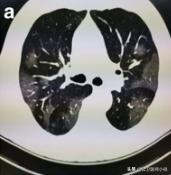

早期CT肺部影像学

在早期胸部影像学改变为肺低玻璃阴影

毛玻璃样阴影